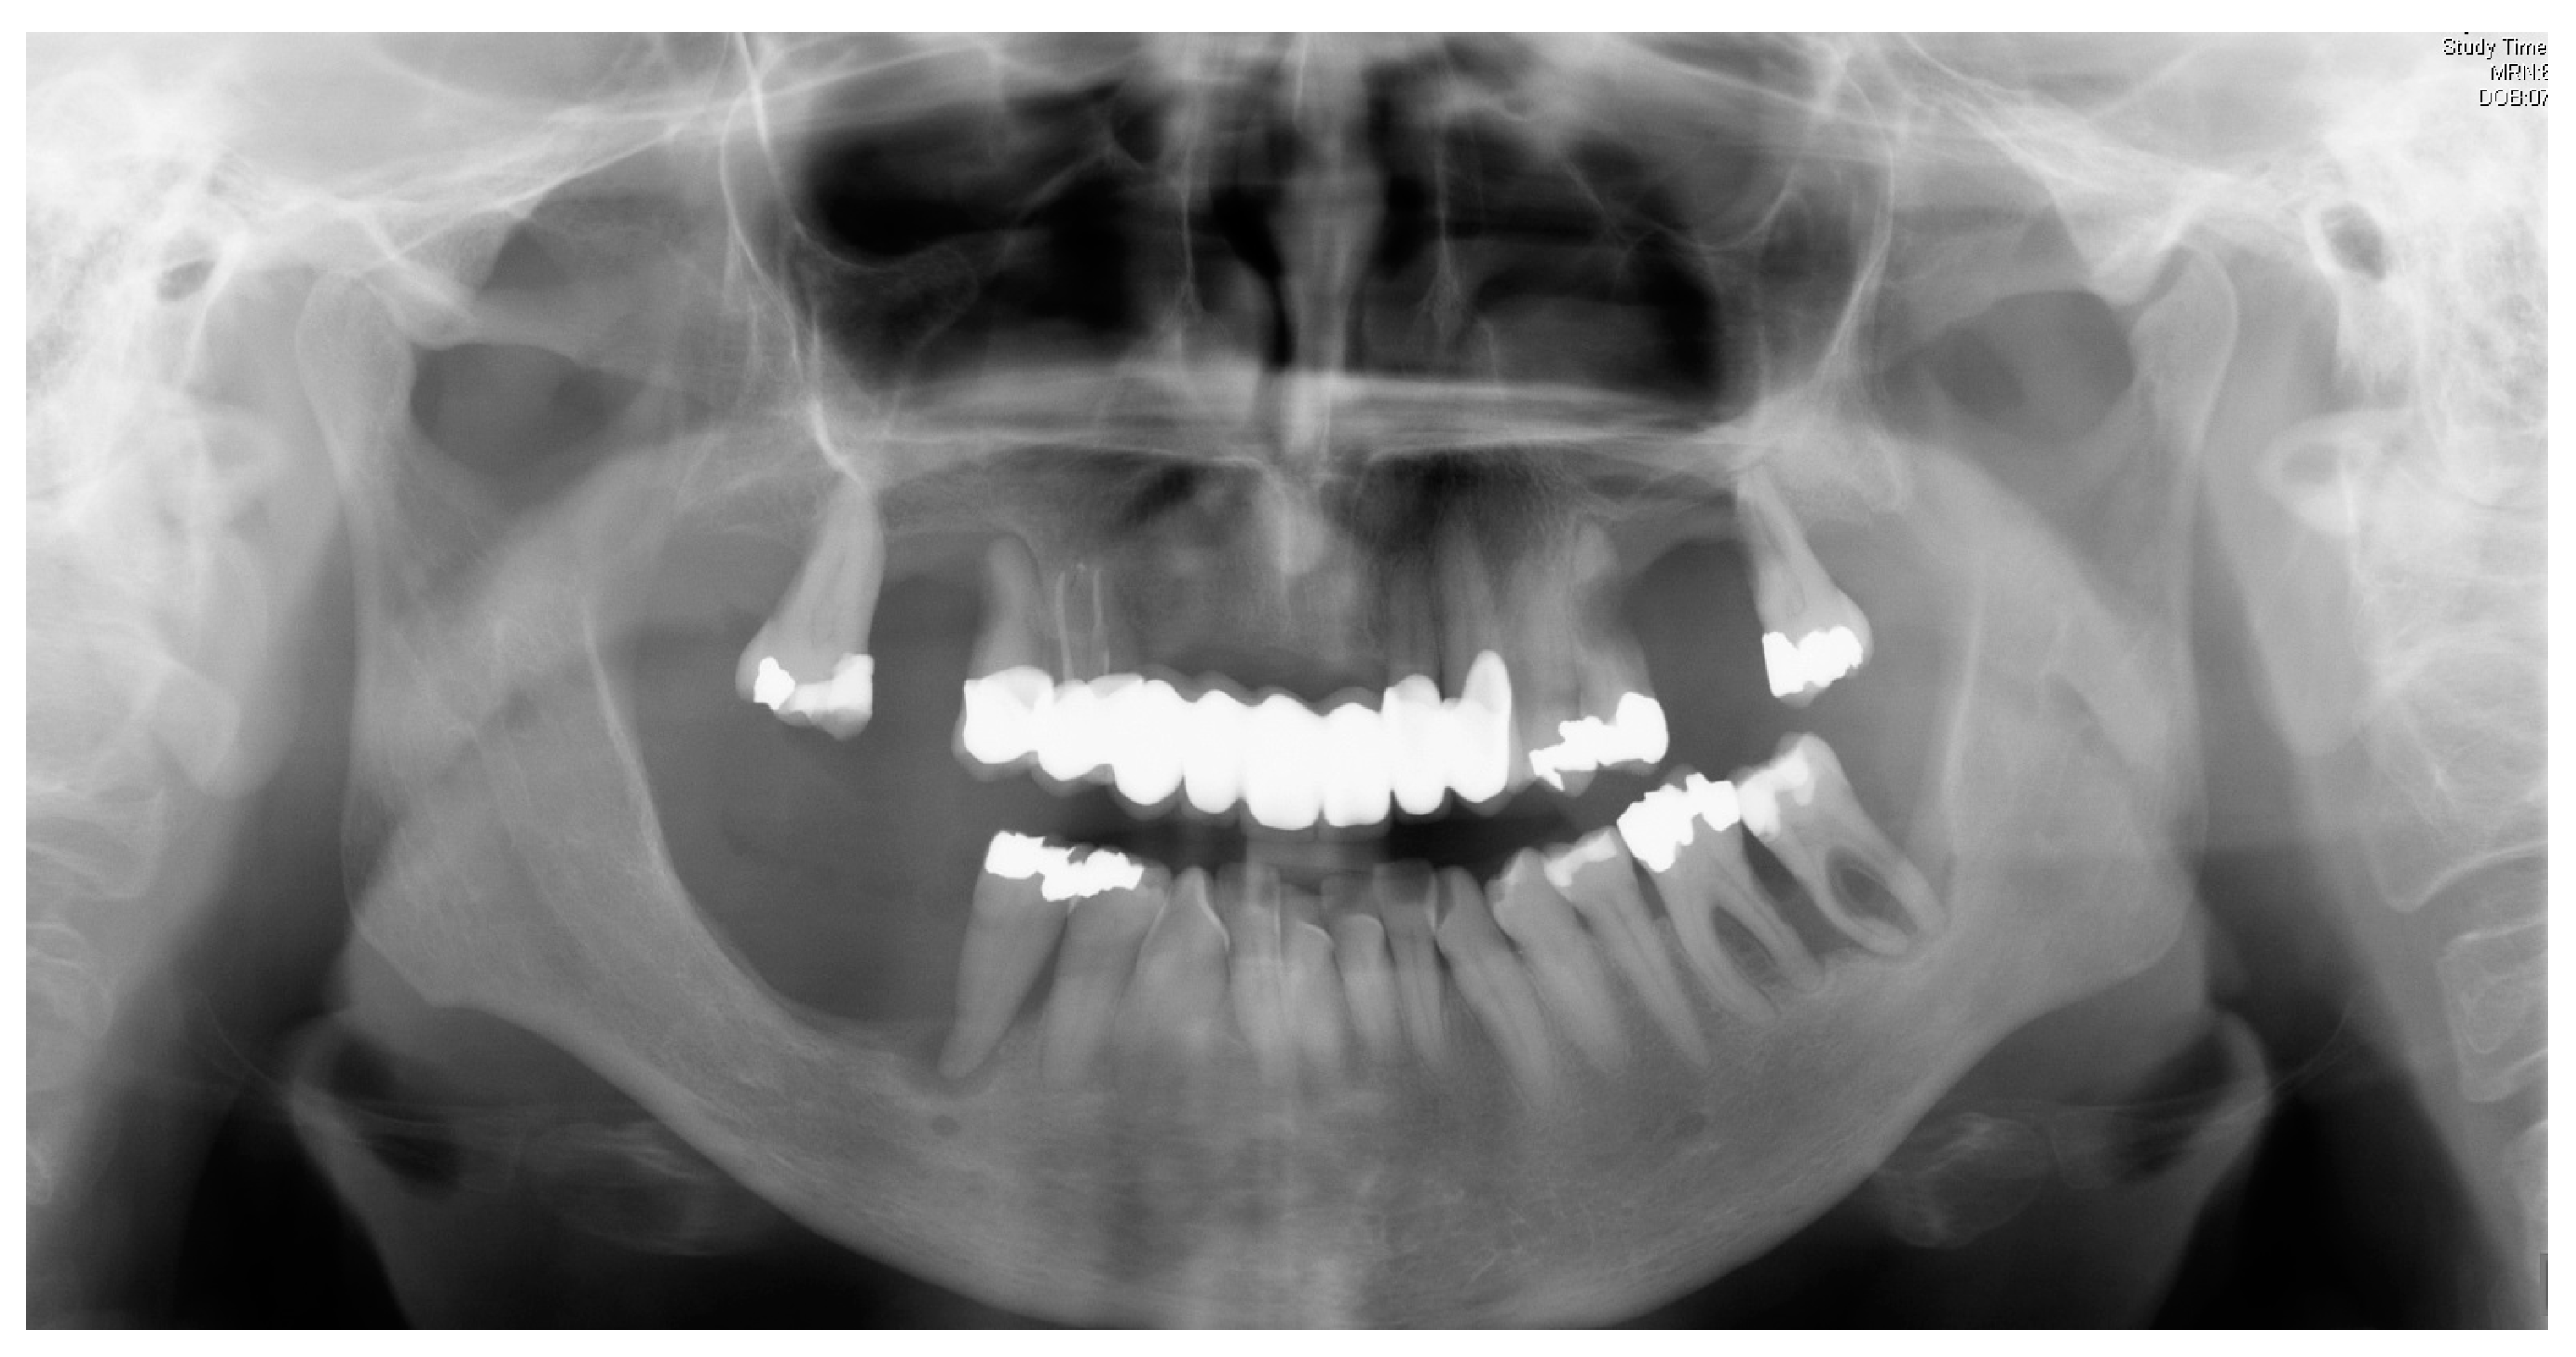

- Hanisch, M.; Jung, S.; Kleinheinz, J. Identification of rare diseases in the oral cavity. Internist 2018, 59, 972–980. [Google Scholar] [CrossRef] [PubMed]